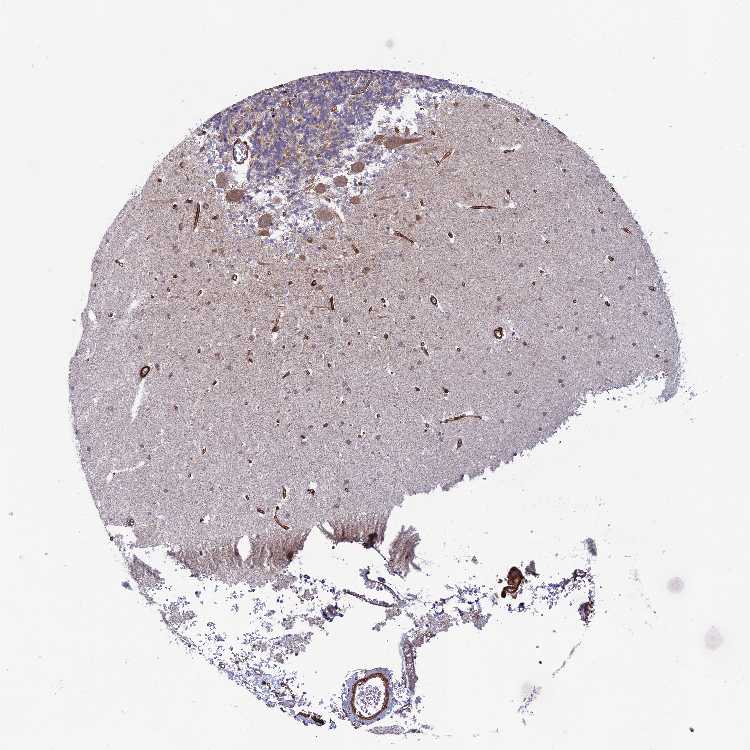

BRAIN CEREBELLUM Show tissue menu

CEREBELLUM - Expression summary

CEREBELLUM - Antibody stainingi

Antibody staining in the annotated cell types in the current human tissue is reported as not detected, low, medium, or high, based on conventional immunohistochemistry profiling in selected tissues. This score is based on the combination of the staining intensity and fraction of stained cells.

Each image is clickable and will lead to virtual microscopy that enables deeper exploration of all samples and also displays staining intensity scores, fraction scores and subcellular localization as well as patient and tissue information for each sample.

Antibody HPA036089Antibody HPA036090Antibody CAB018774

Purkinje cells Not detectedMediumMedium

Cells in granular layer Not detectedMediumMedium

Cells in molecular layer Not detectedLowNot detected